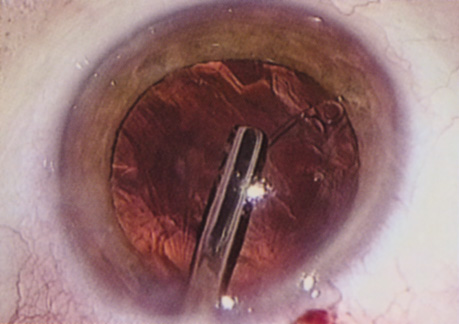

ANTERIOR CAPSULOTOMY

One of the most beneficial techniques developed over the last decade is capsulorrhexis. A continuous curvilinear anterior capsular opening helps prevent intraoperative and postoperative complications. With capsulorrhexis, mechanical strength of the capsular opening is superior to that in a can-opener capsulotomy; thus, a tear to the posterior capsule with subsequent vitreous loss is much less likely.96 Capsulorrhexis allows for nuclear manipulation with less risk of posterior capsule rupture. Cortex removal is made easier as well, because it becomes easier to differentiate cortical material from anterior capsule. Should a posterior capsular tear occur, sulcus fixation is more likely attainable with the presence of a clearly visible residual anterior capsular rim. Placement of both IOL haptics into the capsular bag is more certain with capsulorrhexis because the surgeon can more easily visualize the haptics gliding beneath the anterior capsular rim.

Capsulorrhexis can be performed with a cystitome, capsulorrhexis forceps, or combination-type instruments. Regardless of which instrument is used, several principles can help the surgeon successfully complete capsulorrhexis. It is important to maintain the anterior chamber, because making the chamber shallow increases tension on the zonules and causes the tear to run peripherally. The authors recommend the use of a viscoelastic agent for maintaining chamber depth and, of course, for endothelial protection. Therefore, if the tear begins to run peripherally, the surgeon should redeepen the anterior chamber before attempting to redirect the tear. Additionally, folding the capsule margin can aid the surgeon in redirecting the tear more accurately (Fig. 10).

Fig. 10. The capsulorrhexis tear is more easily redirected by folding the capsule over, in advance of the tear.